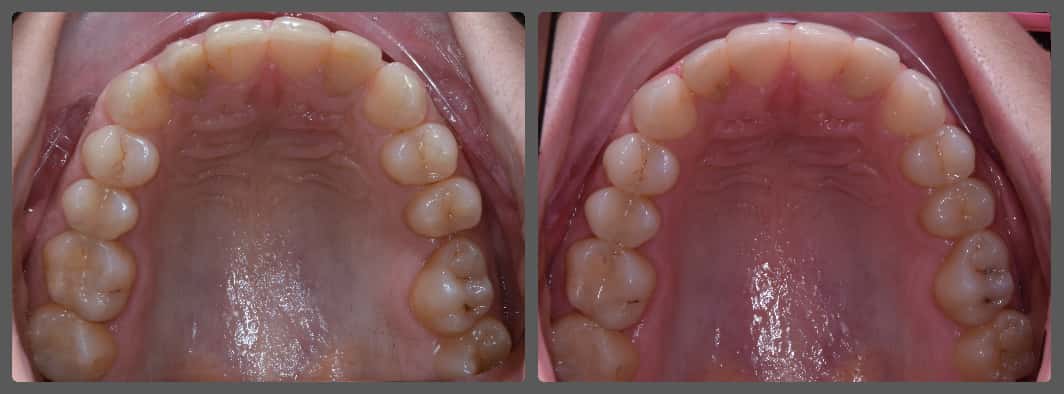

Szonja és szülei torlódott fogazata miatt kerestek fel engem a Semmelweis Egyetemen. Az omega formájú, szűk fogívek mellett enyhe mélyharapást és disztálharapást is diagnosztizáltam nála. Alsó-felső hagyományos készüléket ragasztottunk Szonja fogaira, a mélyharapását harapásemelők segítségével korrigáltam, míg a disztálharapás megoldására intermaxilláris gumihúzást alkalmaztunk a fogszabályzó kezelés során. Bár Szonjának szüksége volt egy kis ösztönzésre, ami a gumihordást illeti, mégis rövid idő alatt értünk el gyönyörű eredményt. Látható, hogy a megfelelő diagnózis felállítását követően, helyes technikákat alkalmazva hagyományos készülékkel is nagyon szép eredményt lehet elérni, ráadásul belátható időn belül! Szonja kezelése 17 hónapig tartott.